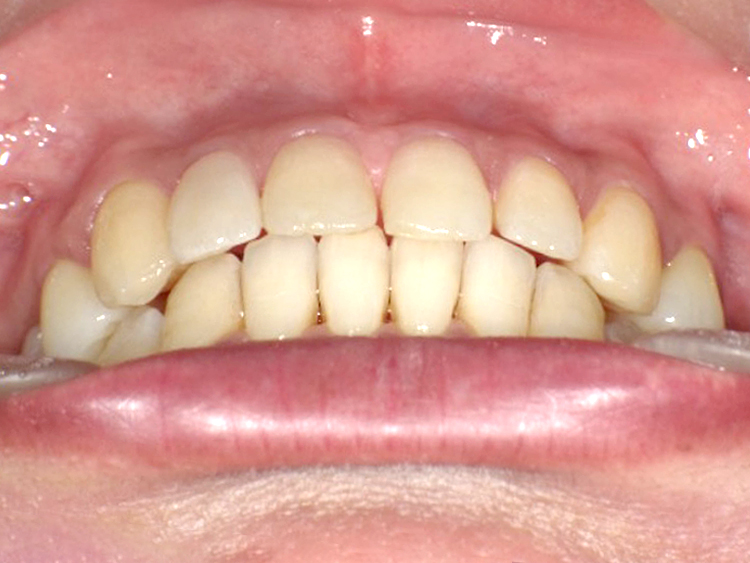

症例4

Before

After

| 主訴 | 上下前歯のがたつき |

|---|---|

| 年齢 | --- |

| 治療 期間 |

約9ヶ月 |

| 治療 内容 |

インビザラインiGoで上下顎の治療。 |

| 治療費 | ¥550,000(税込)/調整料含む |

| 治療のリスク | 矯正終了後は、リテーナーを指示通りに使用し、歯の後戻りを防ぐ必要があります。 |